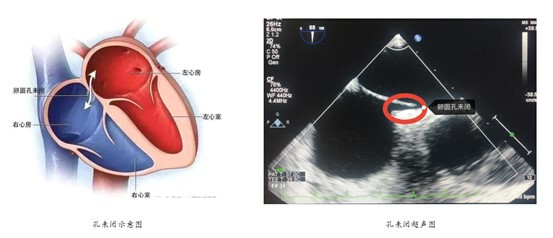

卵圆孔是胚胎时期心脏房间隔卵圆窝处进行血液交换的一个正常生理性通道,正常情况下在婴儿出生后两个月左右融合,若超过3岁还未闭合则形成卵圆孔未闭(PFO)。据《卵圆孔未闭预防性封堵术中国专家共识》数据显示,成人中PFO发病率约25%。在卵圆孔未闭人群中,发生心源脑卒中、偏头痛、动脉栓塞的风险要远远高于正常人群。

心脏卵圆孔